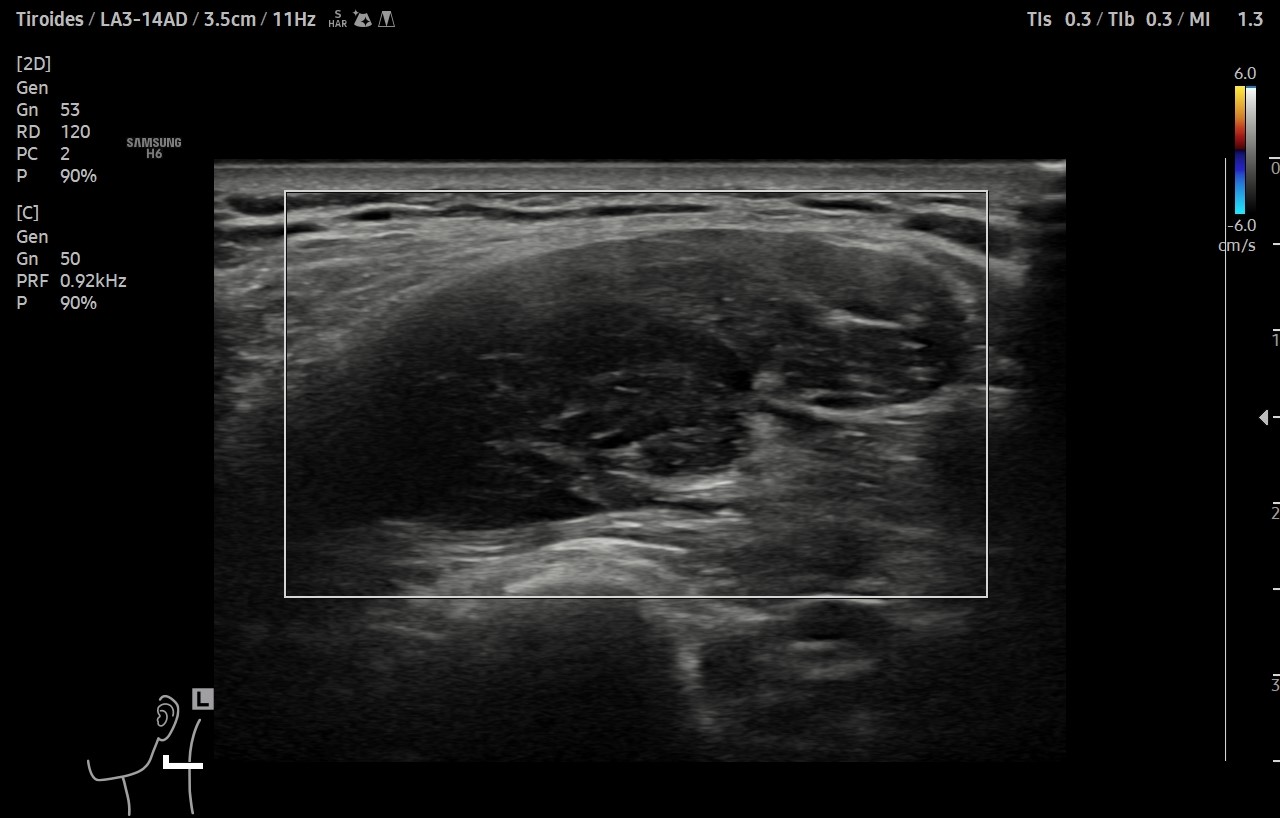

Ante sospecha clínica de malignidad se realiza ecografía.

Hallazgos ecográficos

Ecografía clínica de cuello: objetivando en cara lateral izquierda una imagen hipoecogénica, lobulada, heterogénea y vascularizada al Doppler, de aproximadamente de 3 cm, con apariencia de depender de la capa muscular. Adicionalmente, se detectó un nódulo tiroideo izquierdo con microcalcificaciones, aunque la TSH era normal.